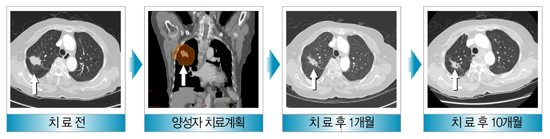

폐암의 양성자 치료 사례